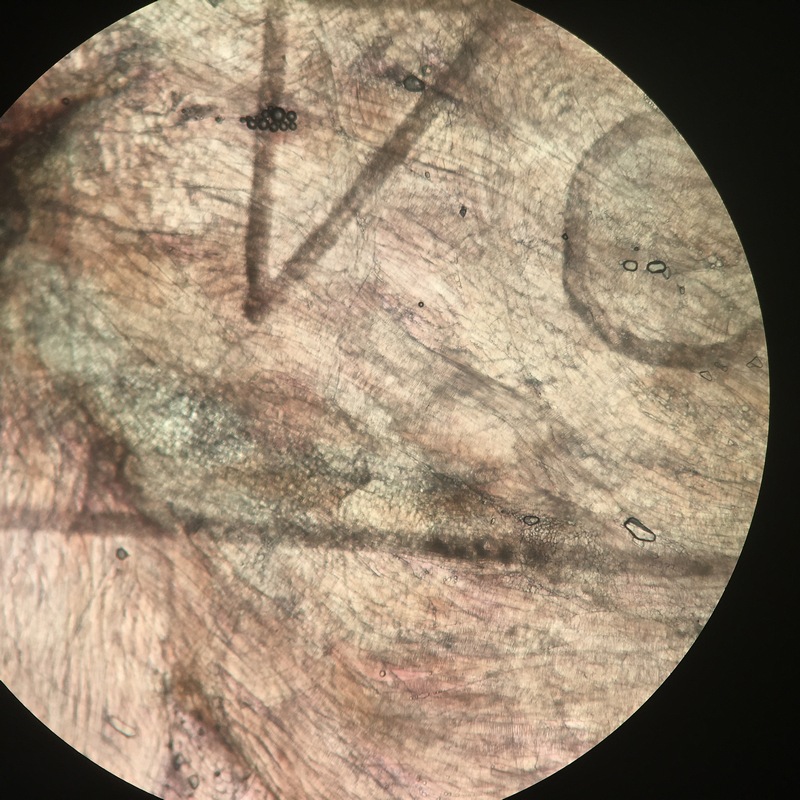

Всем привет! Хочу насчет трихинелл у нашего сурка сказать небольшое слово ). Сегодня ДМБ2011 мне любезно передал мясо от сурка и я посмотрел несколько проб с ребер и с позвоночника (диафрагмы не было). Подходят те мышцы, которые активно работают :). Ну и заодно зафотал части процесса. Использовал компрессорий - два толстых стекла между которыми сдавливается сильно мышечные волокна, стекла фиксируются гайками и всё это дело смотрел под бинокуляром на 25Х увеличении.

Личинок я не увидел. Не увидел - не значит, что их нет. Это значит, что их не было в тех кусках мышц или же, что интенсивность инвазии достаточно низкая. Надо в таких случаях брать больше проб. Использовать другой метод - переваривание.

в том мясе, которое я посмотрел, нематод-трихинелл не обнаружил. Его употреблять можно :). Да и в остальных сурках с низкой вероятностью можно наткнуться на трихинелл